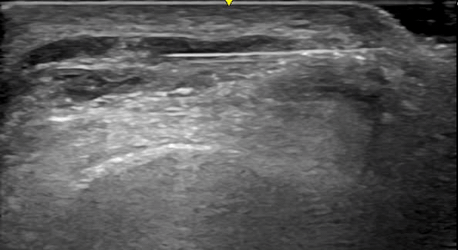

Ultrasound image of an abnormal muscle receiving hydrodissection treatment.

Nerve and muscle hydrodissection is a gentle, non-surgical treatment that helps reduce pain and improve how you move. It works by freeing nerves or muscles that are stuck or irritated. Using an ultrasound to see inside your body, we carefully inject a small amount of sugar water around the tight area. This helps create space, lowers swelling, and lets the nerve or muscle move normally again.